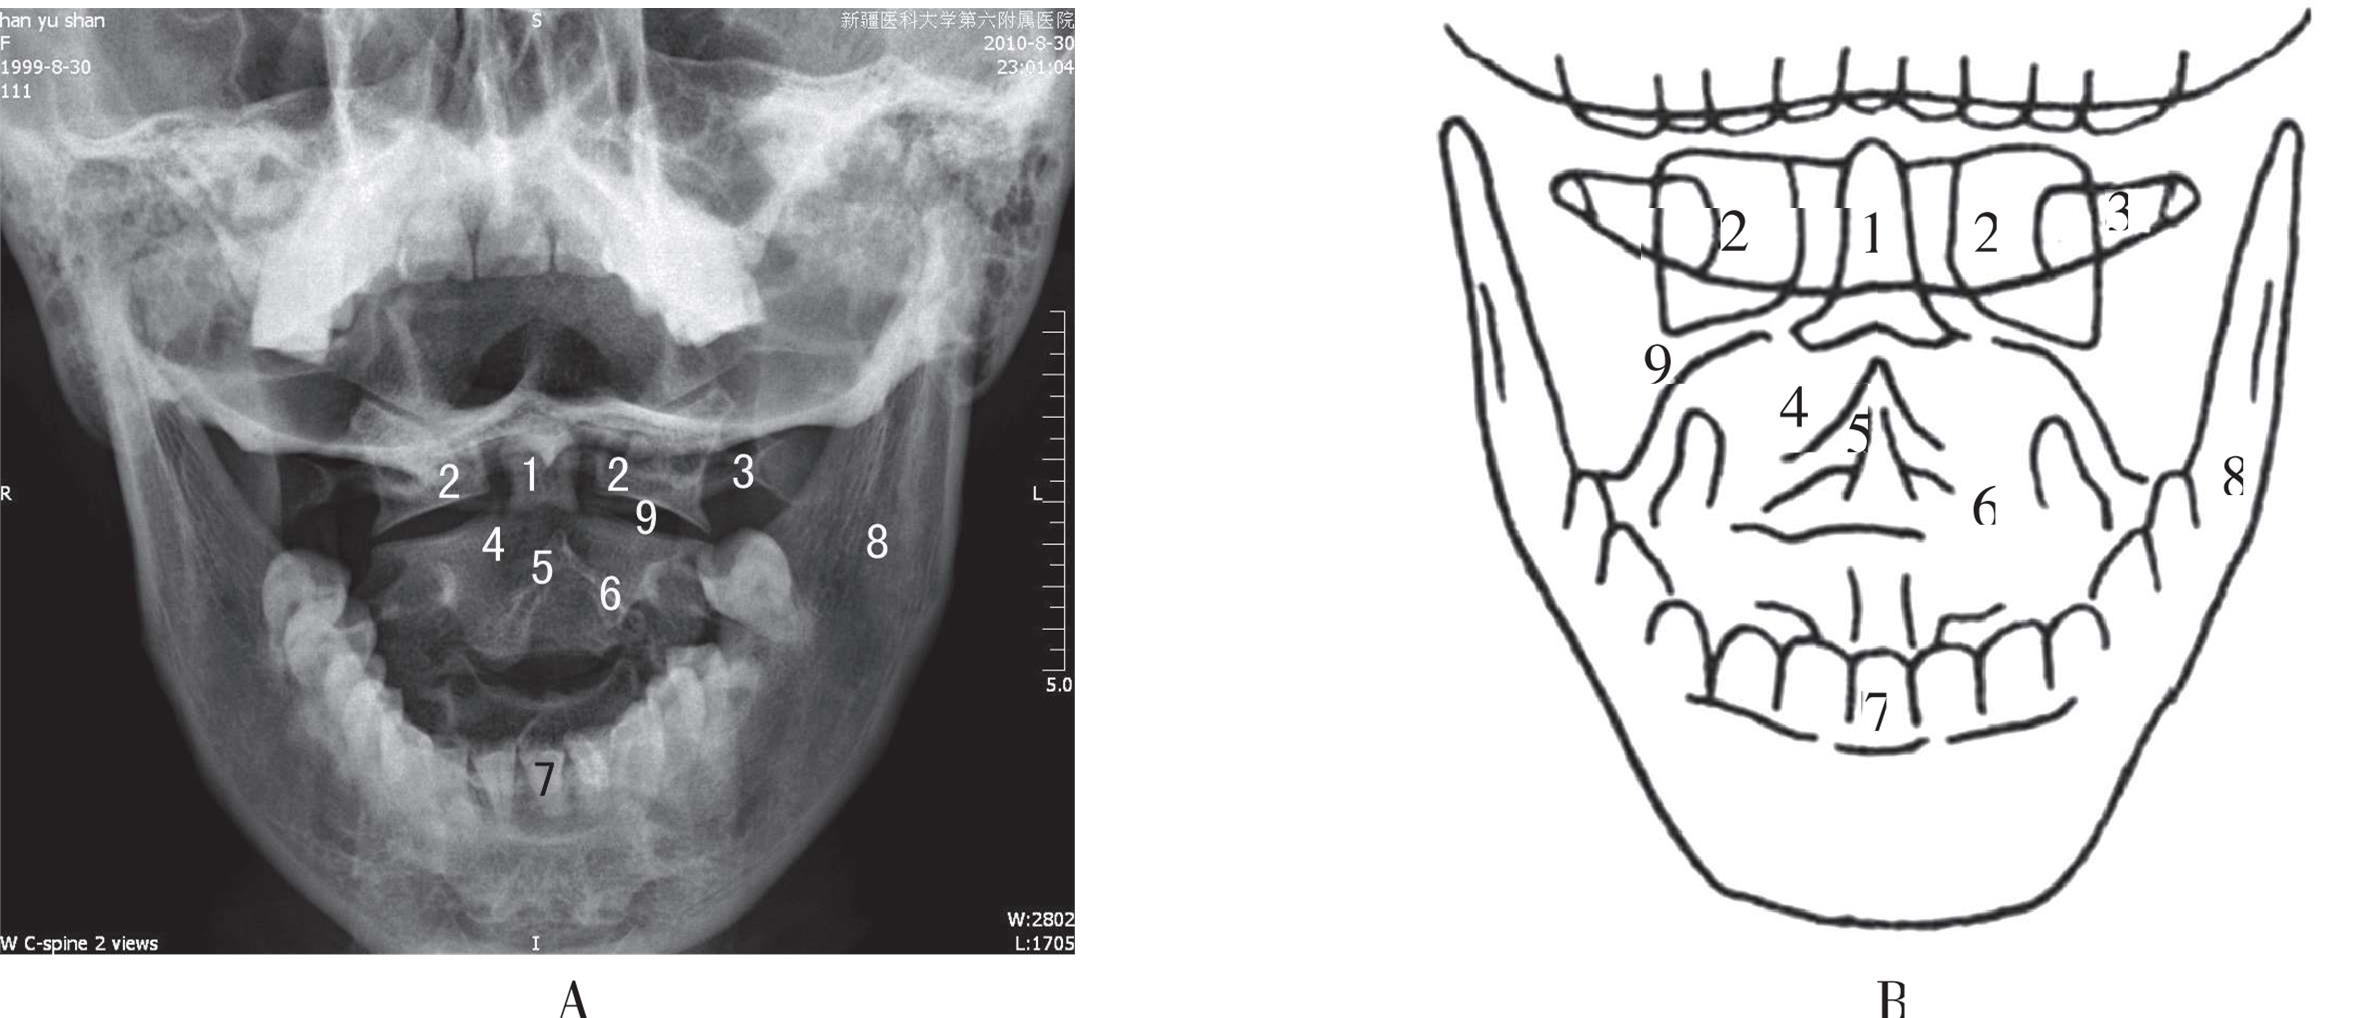

患者取仰卧位于摄影台上,身体正中矢状面与台面垂直,头稍向上仰。尽量张口,不能持久者可以在上下前齿间夹一海绵垫,使上颌切牙咬合面中点与乳突尖连线垂直于台面。上下切牙中点对胶片中心,中心线经上颌切牙咬合面中心垂直摄入胶片。曝光时让患者做“啊”声,以使上下颌张开(图3-3),以免门齿及下颌骨与1、2颈椎重叠,影响显影质量。该投照位置能清晰显示寰椎侧块、枢椎齿状突、寰枢关节、寰枕关节(图3-4)。枢椎齿状突位于寰椎两侧块之间,寰椎横突位于侧块的外部,其下方枢椎的骨质、椎弓、棘突显示清晰。

A. 寰枢椎张口前后位X线片;B. 寰枢椎张口前后位示意图。1. 枢椎齿状突;2. 寰椎侧块;3. 寰椎横突;4. 枢椎椎体;5. 枢椎棘突;6. 枢椎椎板;7. 门齿;8. 下颌骨;9. 寰枢关节间隙

图3-4 寰枢椎张口前后位